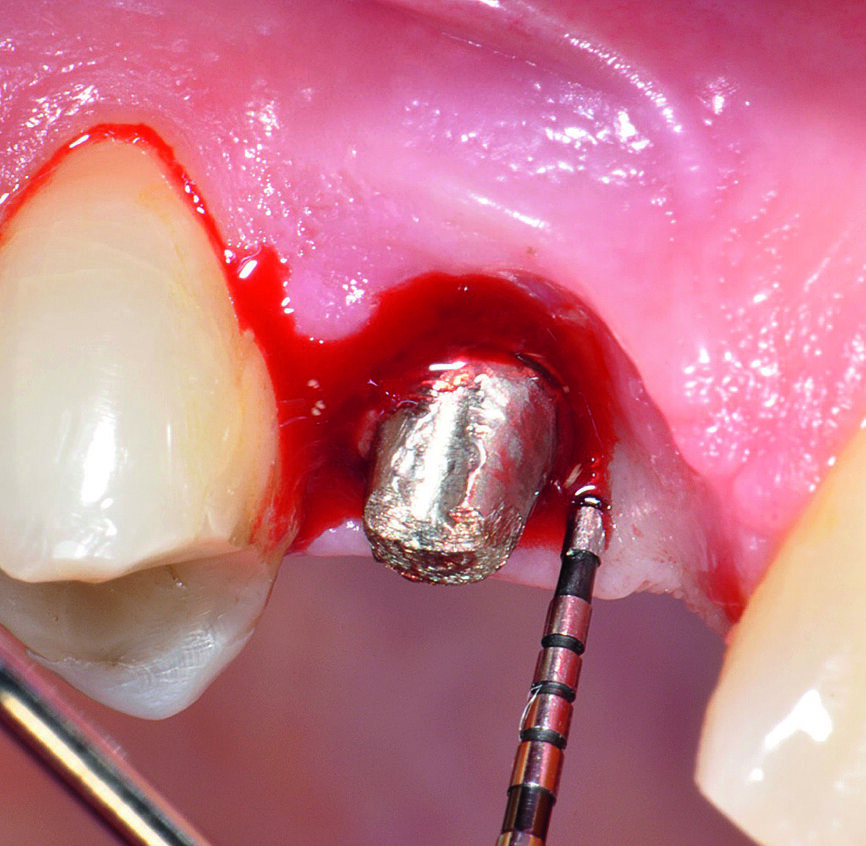

Fig b : Implant en position 14 affecté par une péri-implantite : sondage péri-implantaire après retrait de la couronne prothétique.

Fig. 2 : Radiographie de

l‘implant